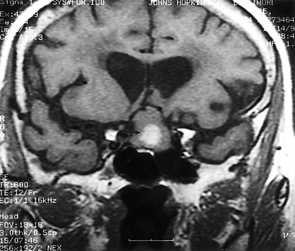

Внутриопухолевые кровоизлияния встречаются редко. обычно они не обширные, как, например, при апоплексиях аденом гипофиза. Апоплексия - это острое нарушение кровоснабжения гипофиза с некрозом или кровоизлиянием. Частота около 10% случаев макроаденом. Клинически апоплексия появляется головными болями, рвотой и зрительными нарушениями. Изредка обширные кровоизлияния наблюдаются в метастазах.

МРТ головного мозга. Корональная Т1-взвешенная МРТ. Апоплексия макроаденомы гипофиза с кровоизлиянием.